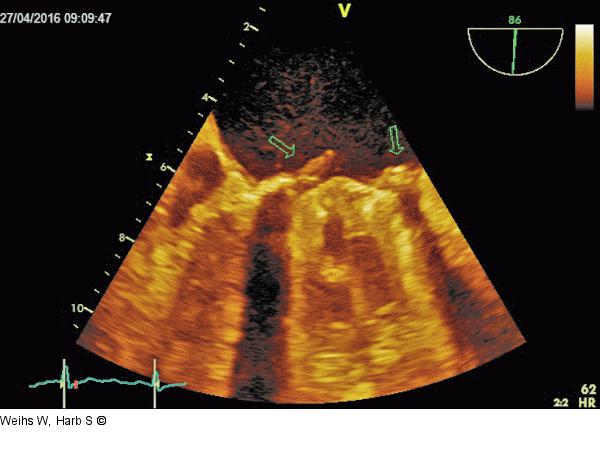

Abbildung 5: TEE Rezidivendokarditis mit Vegetationen an der Mitralklappenprothese. |

Rezidivendokarditis mit Vegetationen an der Mitralklappenprothese. |